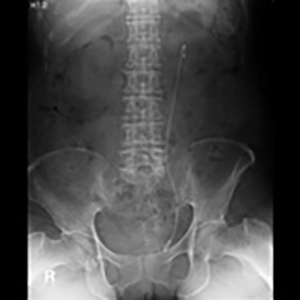

尿管ステント挿入術(ダブルJ)

透視室9番で、泌尿器科医により行われている治療です。

膀胱鏡とX線透視を使いながら尿管口からガイドワイヤーを進めてゆき、腎臓と膀胱をつなぐダブルJ型のステントを留置する手技です。尿路狭窄や尿管結石で尿が流れなくなった場所を開通させます。